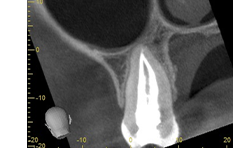

Once the canals are cleaned and shaped to their appropriate size, the root canal system can be obturated. In this case, the tooth was obturated using a warm vertical down pack with Obtura backfill (Figs. 12-15).